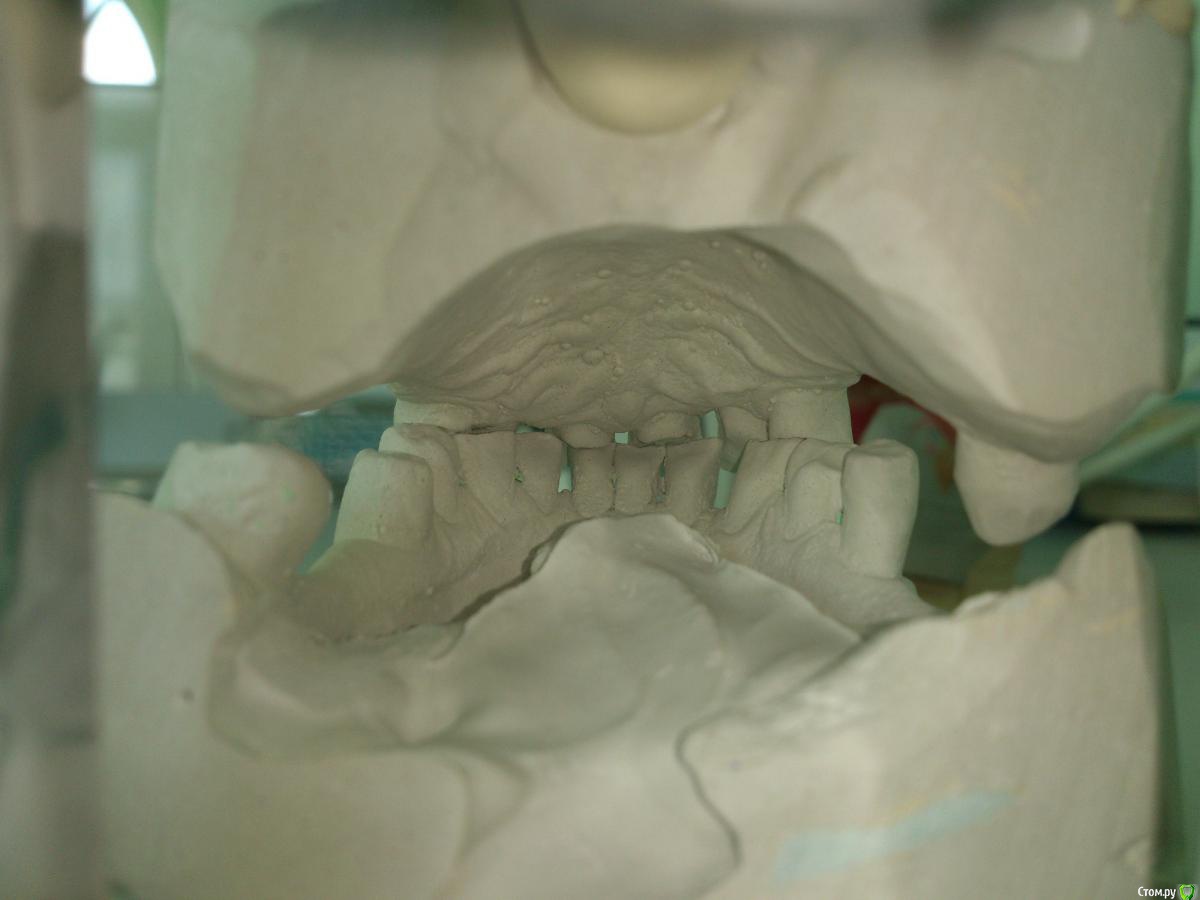

SanderS Опубликовано 16 июня, 2015 Поделиться Опубликовано 16 июня, 2015 Пациентка 1950 г.р. обратилась с жалобами на эстетику и затрудненное пережевывание пищи. 3.1, 4.1, 4.2, 3.7 удалили из-за подвижности , 2.2 так же ушел из-за подвижности и сильного выдвижения.Как быть? В планах: ВЧ - вкладки+МК мост+бюгель замки, НЧ - МК мост+бюгель замки. Сомневаюсь по поводу замков, может лучше опорно-удерживающие? Или вообще рассмотреть имплантацию, но хирург в отпуске, КТ заканчивают ремонт, а пациент просит завершить к концу июля. Ссылка на комментарий

Larnary Опубликовано 16 июня, 2015 Поделиться Опубликовано 16 июня, 2015 (изменено) Ну полноценный план лечения давать без элементарной панорамы не серьезно. А что закончить всю работу до конца июля,если речь идет о качестве-лично я бы попрощался с таким пациентом.почему так категорично,работа не простая и может быть немало подводных камней и загонять себя в узкие рамки опрометчиво. Но в любом случае пациенту сначала надо объяснить всю ситуацию и сказать,что для качественного лечения может потребоваться значительно больше времени,особенно,если договоритесь об имплантации.по-поводу замков,чую по моделям и причине удаления зубов,там беда с пародонтом,а потому замки не лучший способ восстановления.А вот,что лучше...ждем снимки Изменено 16 июня, 2015 пользователем Larnary 2 Ссылка на комментарий

krokomot Опубликовано 16 июня, 2015 Поделиться Опубликовано 16 июня, 2015 Я бы на вашем месте, сначала опеределил снижение высоты прикуса, в зависимости от результата, в случае качественных опорных зубов изготовил бы сьемный протез на верх и низ, что вписывается в ваши временные рамки. На нем поднять высоту, номожно приплюсовать временные коронки, но опять же понорамы нет что с каналами? Ссылка на комментарий